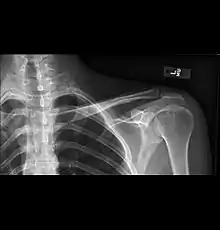

AP radiograph demonstrating companion shadow of the clavicle

• Clavicular companion shadow is a thin soft-tissue stripe along the upper edge of the clavicle.[1]